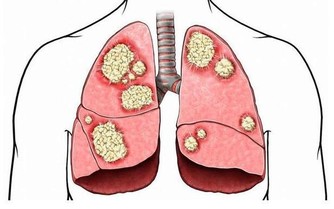

不僅咳嗽,還有胸悶、痰中帶血的情況,可能是心臟和肺部出現嚴重問題,常常因為咳嗽不能安穩入睡,家長要重視起來。

不僅咳還有點喘,有“吼”聲,暗示肺部問題有點嚴重,建議找醫生處理,不要亂吃止咳藥。

家長要留心孩子的心肺功能,若是發現孩子最近一段時間總是清嗓子,不喜歡外出運動,體力下降了,可能是肺功能降低了,建議進一步到醫院確診。